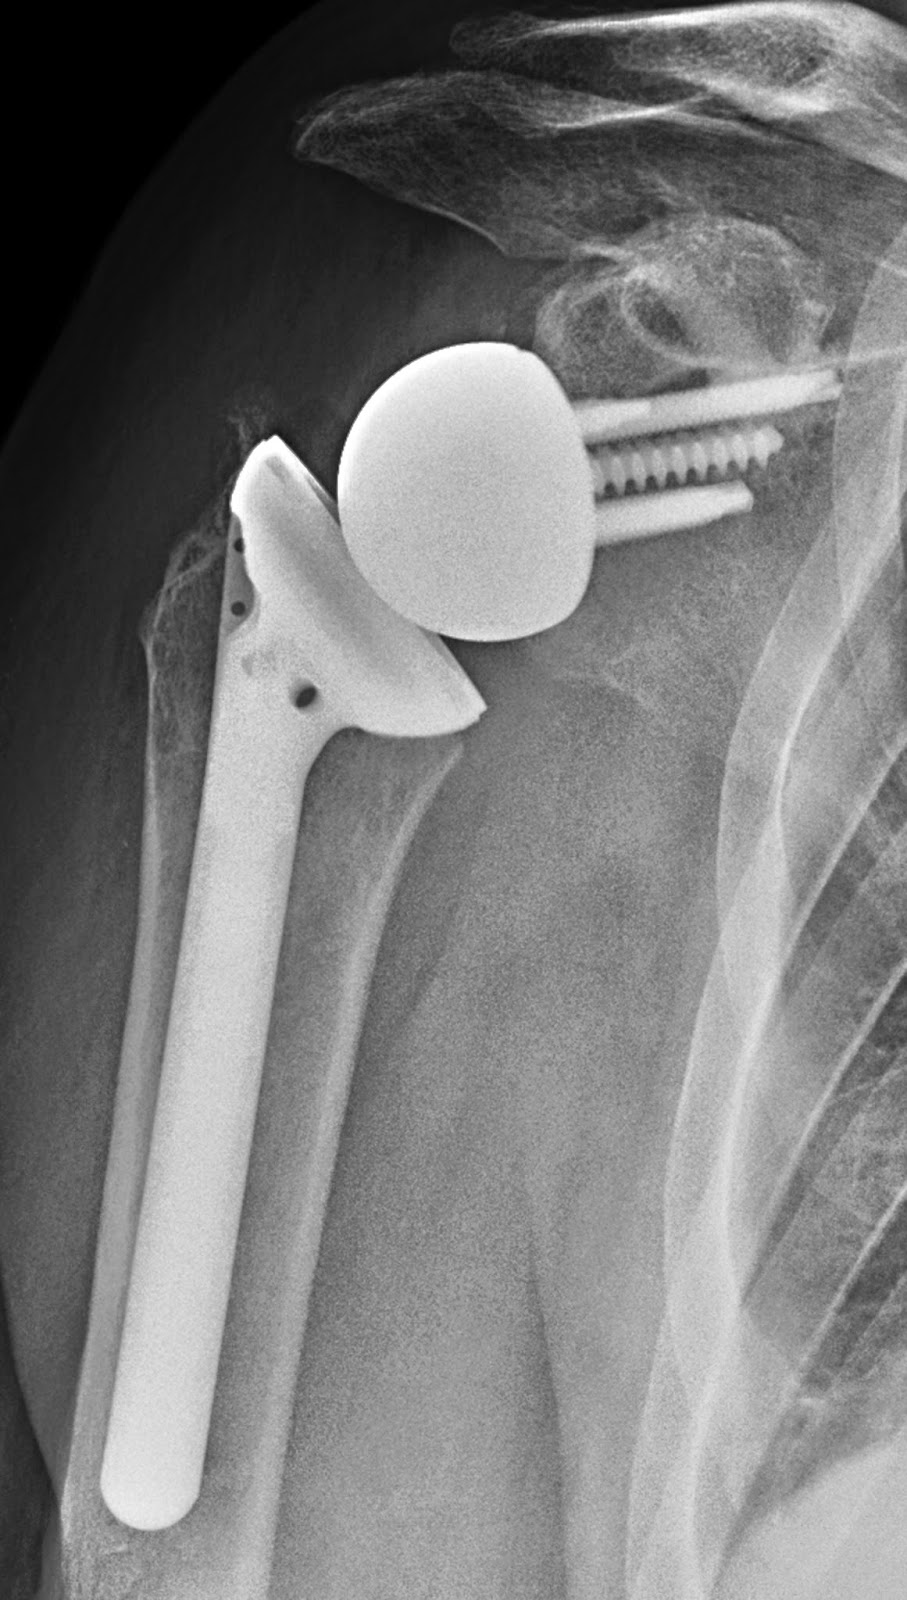

UW Shoulder and Elbow Academy Reverse total shoulder joint replacement Arthritis And Total Joint Replacement total joint replacement is a surgical procedure in which parts of an arthritic or damaged joint are removed and replaced. joint replacement surgery is a procedure in which a surgeon removes a damaged joint and replaces it with a new,. What to expect before, during, and after surgery and during your. Just as medical treatments changes, so do. Arthritis And Total Joint Replacement.